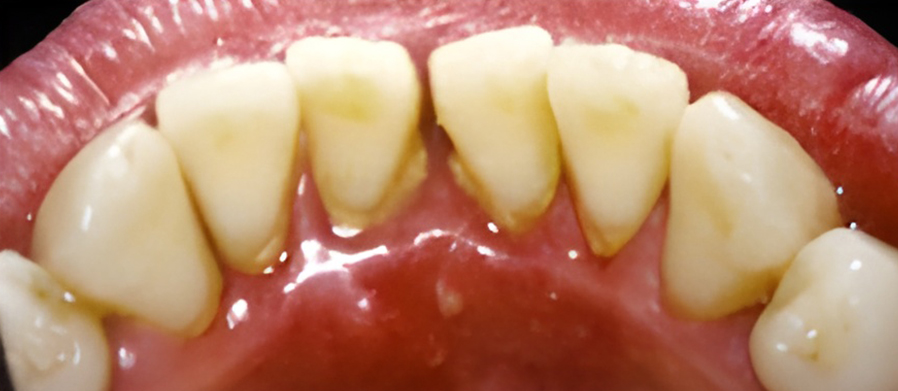

칫솔질과 치실질을 통해 매일 플라그를 제거하지 않으면 박테리아로 인해 잇몸 조직이 붉어지고 부어오르게 됩니다. 염증이 더 심해지면, 치아 주위 조직에 염증이 생기는 치주염으로 진행될 수 있습니다.

보통 치은염은 칫솔질을 꼼꼼하게 열심히 하고 치실을 사용함으로써 건강한 잇몸을 회복할 수 있습니다. 올바른 칫솔질과 정기적인 스케일링으로 세균이 자랄 수 있는 환경을 제거하면 잇몸을 건강하게 유지할 수 있습니다.